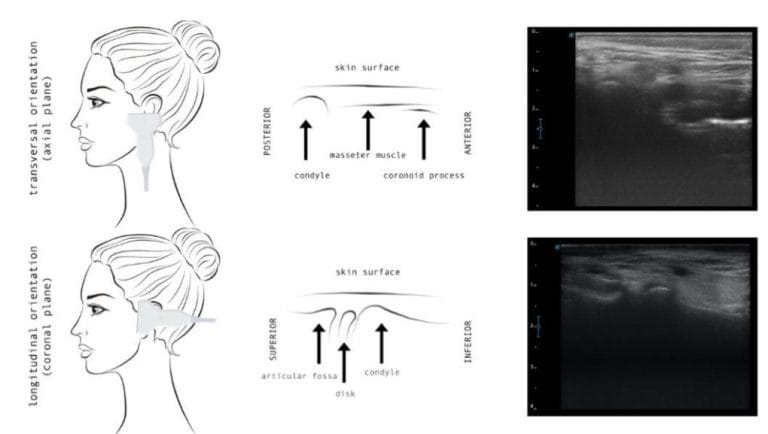

ATM PRO

O caminho para precisão diagnóstica.

Curso avançado com Dr. Ricardo Tesch para diagnóstico e tratamento da osteoartrite da ATM, utilizando ressonância magnética e ultrassonografia.